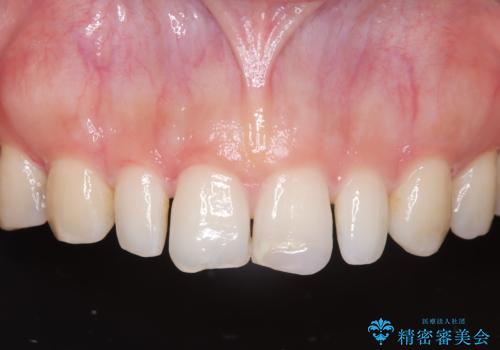

- 歯並びを矯正で整えたあと、上顎左右2番の歯(前歯の横の歯)の「矮小歯(歯が小さい状態)をオールセラミッククラウンで審美修復した症例です。

矯正によって歯並びはきれいに整いましたが、前歯全体のバランスをより自然で美しく仕上げるため、上顎左右2番にオールセラミッククラウンによる審美修復を行いました。

矮小歯はもともと歯が小さいため、削る量を最小限に抑えた負担の少ない治療が可能です。

また、自然な色合いや形になるよう、歯科技工士と連携し、写真を撮影しながら細かく色合わせを行い、周囲の歯になじむよう丁寧に仕上げています。

矯正治療後に、「歯の大きさや形が気になる」「前歯の完成度をもう一段階上げたい」という方に適した治療です。